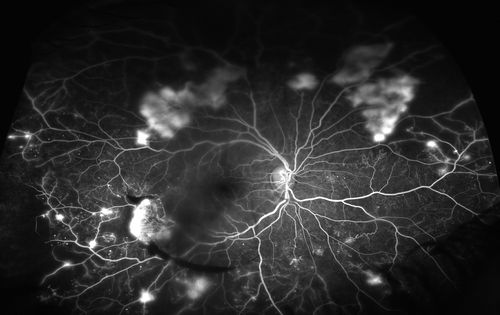

4. Diabetic Retinopathy

Diabetic retinopathy is a complication of diabetes that affects the blood vessels (Microvasculature) of the retina.